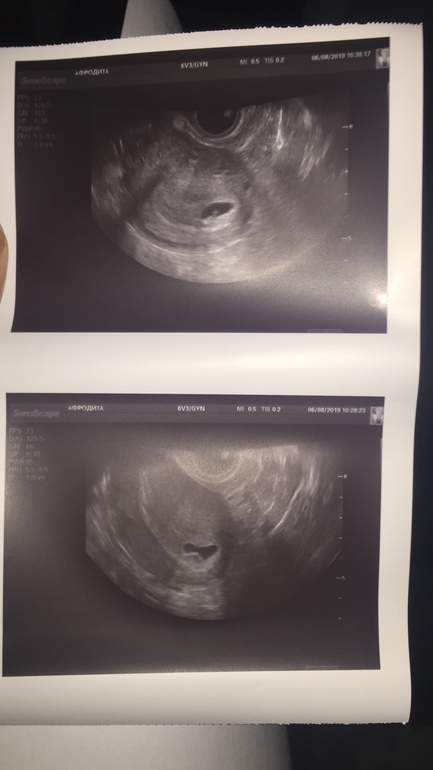

Узи

есть ли шансы ??

По месячным сегодня 6,3

У вас есть беременность, прогрессирующая

Есть эмбрион, живой

На 6 неделе редко ЧСС считают, главное его наличие

Отслоек нет, гематом тоже

И очень большие. Узи вагинально? Левый яичник совулировал?

А ЧСС на таком сроке не все считают, смотрят только, что СБ + и ок.

Неправильная форма ПЯ от тонуса скорее всего.